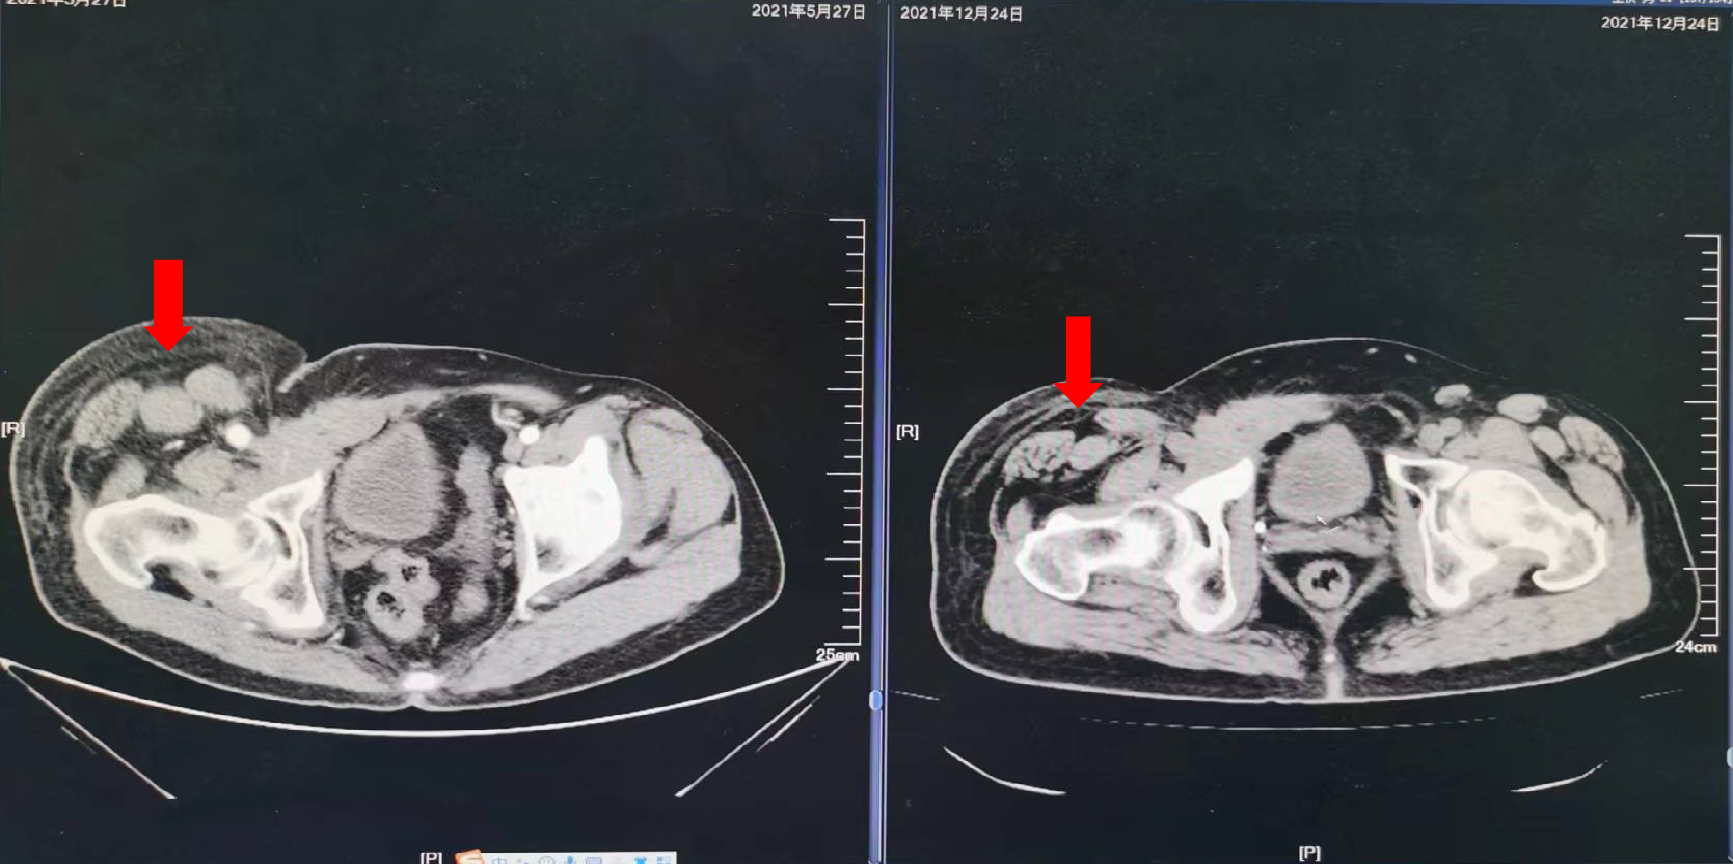

2018年6月:复查腹部CT示:右腹股沟淋巴结肿大;穿刺活检:转移性腺癌,符合结肠来源。

2018年10月29日:复查腹部CT:前腹壁下部可见不规则软组织密度肿块,范围约4.8cm*4.2cm,与后方髂外动静脉分界不清。开始行XELOX方案化疗6周期(奥沙利铂200mg d1+卡培他滨1500mg每日2次*14)。

2021年1月6日:于辽宁中医药大学附属医院肿瘤科住院,右腹股沟肿胀疼痛明显,行动受限,复查彩超提示右侧股浅及腘静脉血栓形成(右侧股总、大隐静脉无法探及),予强阿片类药物止痛及利伐沙班口服抗凝治疗。

2021年5月27日:开始口服曲氟尿苷替匹嘧啶片(TAS-102)55mg每日2次 d1-5,d8-12,Q4W配合信迪利单抗免疫治疗。

疗效评价:SD,患者右腹股沟肿胀疼痛明显减轻,停用止痛药,PFS时间为10个月,主要不良反应为Ⅱ度骨髓抑制。